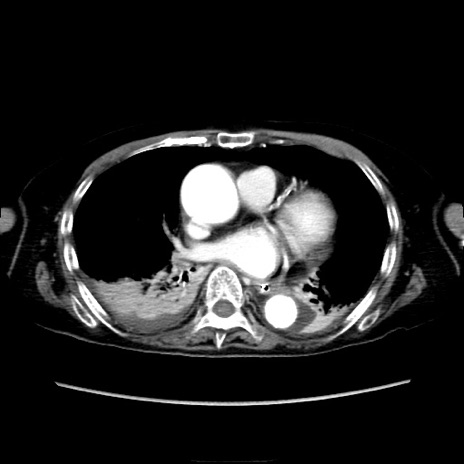

【症例】90歳代女性

【主訴】腹痛・嘔吐

【現病歴】 食欲低下、嘔吐があり昨日他院受診。肺炎と診断され入院となる。入院後より腹部全体に圧痛あり。胃管留置され経過みていたが、症状持続するため、

当院転院となる。

【既往歴】胸椎圧迫骨折、胆石症

【身体所見】腹部:中央に激痛あり、圧痛あり、反跳痛不明

【データ】WBC 17100、CRP 18.82

他院CT